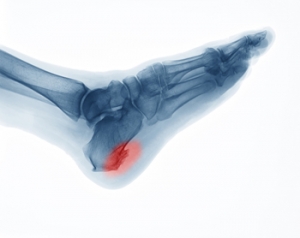

Heel spurs, also referred to as calcaneal spurs or osteophytes, are calcium deposits that develop on the heel bone over time. They typically form in response to chronic strain or tears to the plantar fascia tissue that connects the heel with the toes, or to damage to the heel bone membrane. Other factors that may contribute to heel spurs developing include obesity, wearing improper shoes, age, trauma, training on hard surfaces, or having plantar fasciitis (damage to the plantar fascia) or certain medical conditions. Heel spurs develop on the part of the heel that is closest to the arch, and they point towards the middle of the foot. Heel spurs can be up to a half inch long and are usually only detectable with an X-ray. Heel spurs are usually not painful. When they are, a podiatrist can treat them with rest, ice, orthotic devices and/or shoes, anti-inflammatory medication, cortisone injections, or even surgery if necessary (to remove the spurs).

Heel spurs are formed by calcium deposits on the back of the foot where the heel is. This can also be caused by small fragments of bone breaking off one section of the foot, attaching onto the back of the foot. Heel spurs can also be bone growth on the back of the foot and may grow in the direction of the arch of the foot.

Heel spurs are calcium deposits that cause bone protrusions on the heel bone. Heel spurs are usually associated with plantar fasciitis, which occurs when the plantar fasciitis in the foot becomes inflamed. Typically, heel spurs don’t cause any symptoms. However, they can produce chronic or intermittent heel pain. Those who have had the condition often describe the irritation as a stabbing pain.